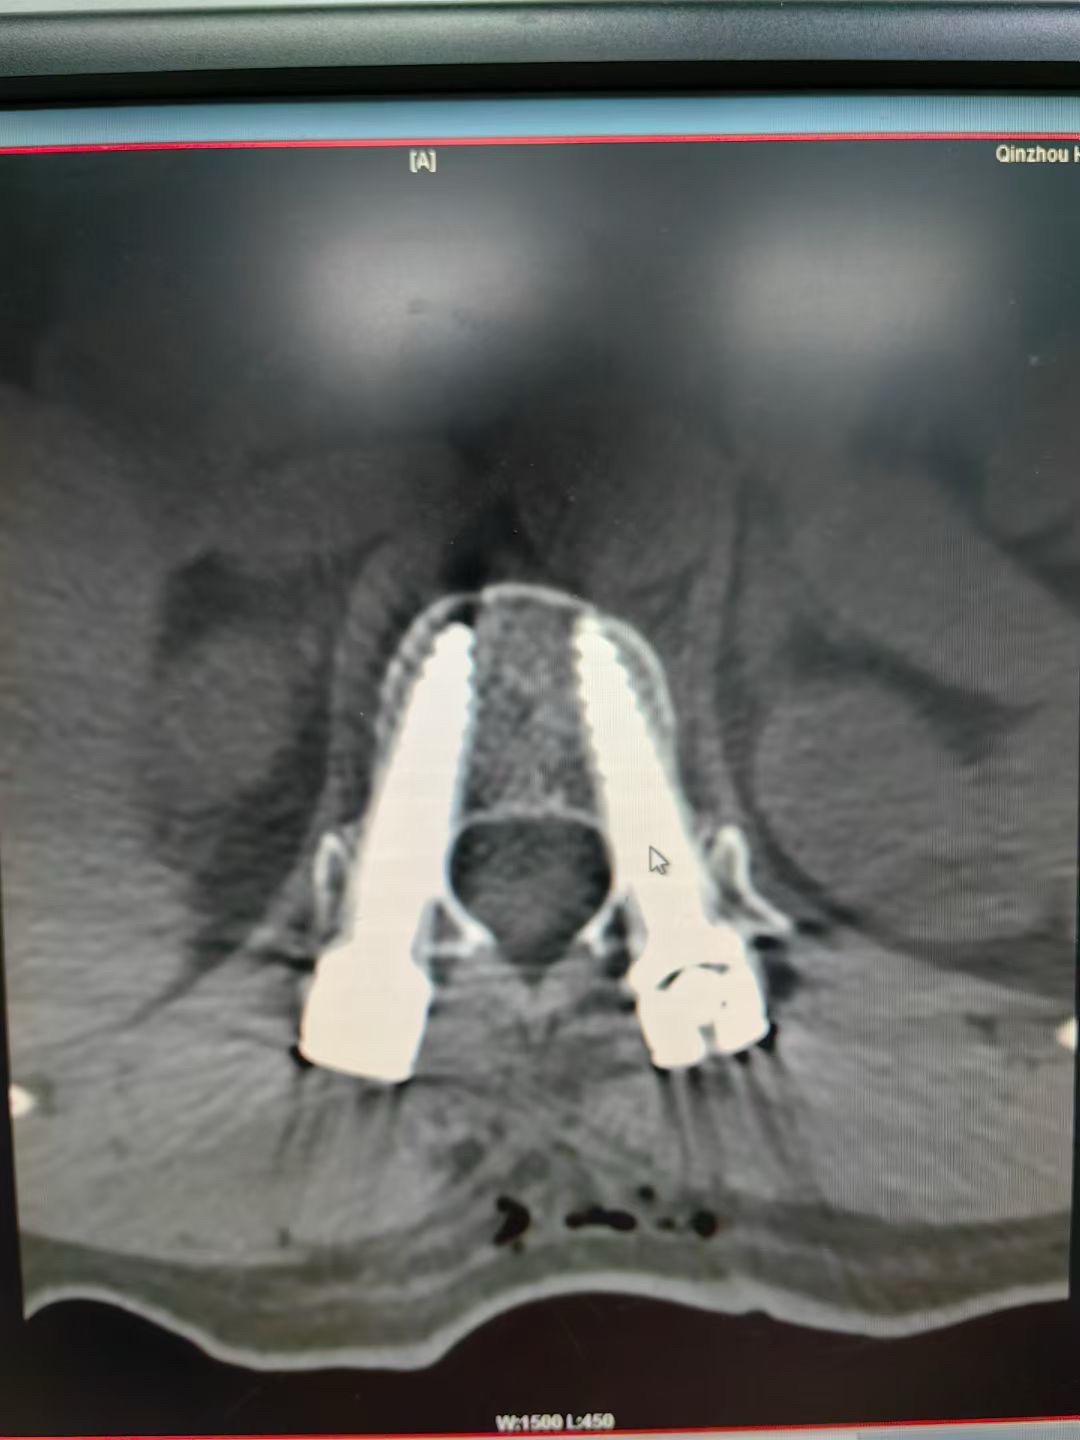

腰1爆裂性骨折,通过闭合复位也是能达到理想的

62岁外伤导致腰3爆裂性骨折,闭合复位,椎体复位稍差,但是椎管的复位还是满意